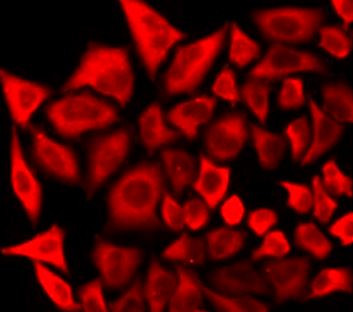

| Application: | ICC, IF, IHC (paraffin), WB |